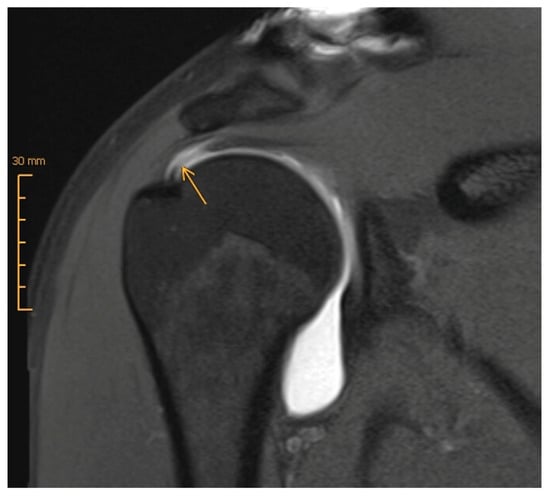

3.1. Magnetic Resonance Imaging (MRI) versus MR Arthrography (MRA)

- Meyer, D.C.; Wieser, K.; Farshad, M.; Gerber, C. Retraction of Supraspinatus Muscle and Tendon as Predictors of Success of Rotator Cuff Repair. Am. J. Sports Med. 2012, 40, 2242–2247. [Google Scholar] [CrossRef]